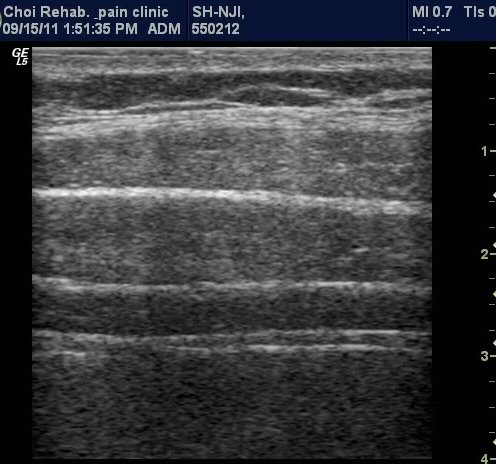

¹è²Å ¿ÜÃø¿¡ ÆÀÃËÀÚ¸¦(ŽÃËÀÚ 1) ´ë°í º¹±ÙÀ» °üÂûÇÔ ¸ð½À, ¼¼ÃþÀÇ º¹±ÙÀÌ °üÂûµÇµµ

°¡Àå ½ÉºÎ¿¡ Ⱦº¹±ÙÀÌ °üÂûµÇ°í ÀÖ´Ù(±×¸² 1). ¼Òº¯À» ÂüÀ¸¼¼¿ä, °ñ¹ÝÀ» ¸Ó¸®ÂÊÀ¸·Î ¿Ã¸®¼¼¿ä,

¹è²ÅÀ» ¹Ù´ÚÀ¸·Î ³»¸®¼¼¿ä µîÀ¸·Î À¯µµÇÑ »óÅ¿¡¼­ Ⱦº¹±ÙÀÇ µÎ²²°¡ µÎ²¨¿ö Áø »óÅÂ(±×¸² 2, 3,

µ¿¿µ»ó 1, 2). ŽÃËÀÚ¸¦ Ä¡°ñ »óºÎ(ŽÃËÀÚ 2)¿¡ ´ë°í ¹æ±¤À» °üÂûÇÑ »óÅ¿¡¼­ °ñ¹Ý ¹Ù´ÚÀÇ ±ÙÀ°À»